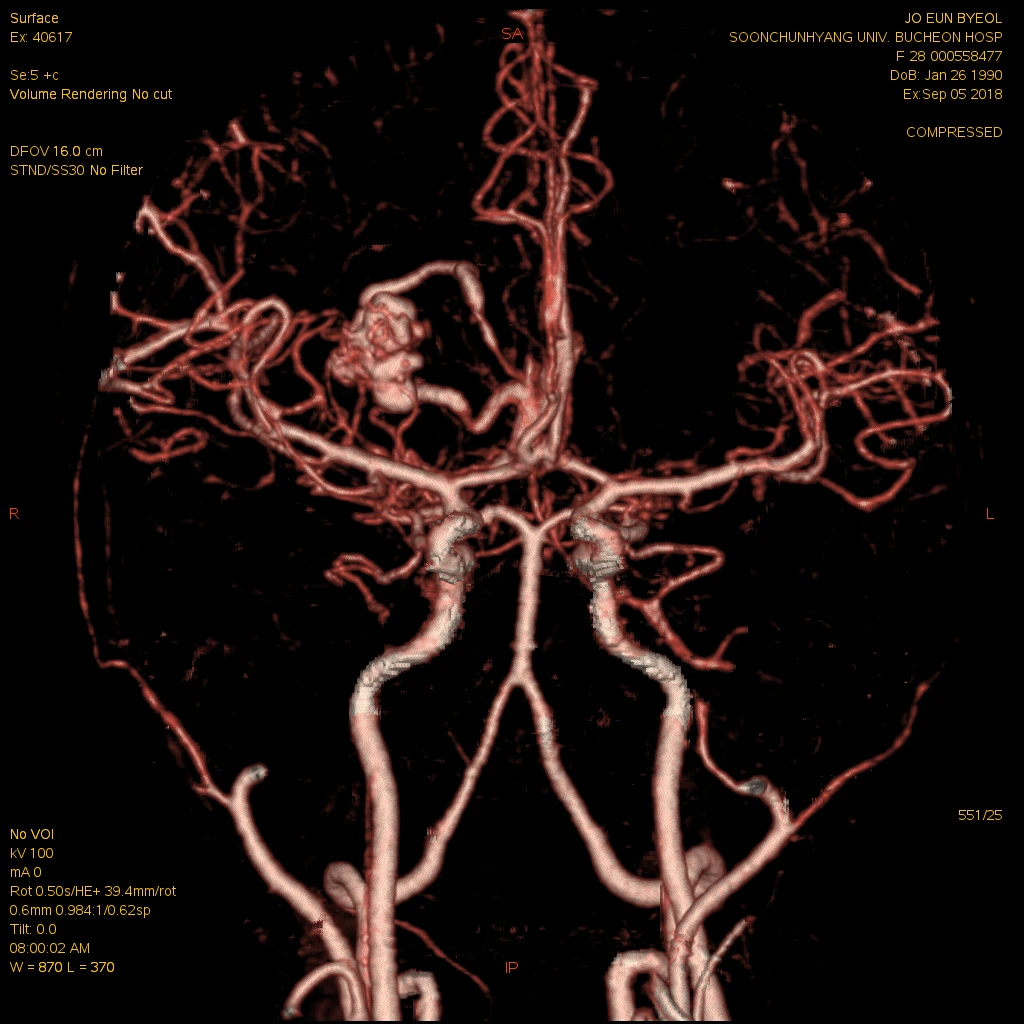

내가 정식으로 진단받은 병명은 ‘동정맥기형 파열에 의한 뇌내출혈’이다. 나는 뇌혈관이 터져버리는 출혈성 뇌출혈로 진단받았고, 출혈 부위는 대뇌, 그 중에서도 기저핵과 시상일부로 여러 부위에 걸친 대형의 기형혈관이 터지면서 뇌손상을 입었다. 고혈압이나 당뇨 등 기저질환을 앓고 있지도 않았는데 갑작스런 뇌출혈로 고생하는 젊은 뇌졸중 환자들은 대부분 이 동정맥기형 때문인 것 같았다.

동맥에서 모세혈관을 거쳐 정맥으로 흐르는 것이 정상인 혈류가 모세혈관을 거치지 않고 동맥에서 정맥으로 직접 흘러서 생기는 비정상적인 혈관의 집합체를 말한다. 중간에 이상 혈관 덩어리인 혈관괴(血管塊)가 생긴다. 주로 대뇌의 표면부에서 안쪽으로 걸쳐서 생기지만 깊은 부위에서 생길 수도 있다. 혈관괴는 성장함에 따라서 조금씩 커지며, 동정맥기형 내의 혈류 속도도 점점 빨라진다. 남자가 여자보다 약간 더 많이 발생하며, 유병률은 0.14%가 조금 넘는 것으로 알려져 있다. 발병연령은 약 33세 전후로 이 가운데 64%가 40세 이전에 진단을 받는 것으로 알려져 있다. 다음의 4가지 신경학적인 증세가 나타난다. ① 뇌출혈 : 동정맥기형이 파열되어 나타나는 증세로 30세 이전에 일어나는 뇌출혈의 가장 많은 원인을 차지한다. 갑작스러운 구토, 두통, 반신마비, 의식변화 등이 생긴다. 출혈이 일어날 때마다 신경학적인 결손을 나타내는 경우가 30∼50%, 사망률이 10%인 것으로 알려져 있다. ② 전간 : 뇌동정맥기형이 주위의 조직을 자극하여 일어난다. 나이가 어릴수록 전간이 일어나는 경우가 많다. 많이 발생하는 연령은 약 25세로 알려져 있고, 뇌동정맥기형의 크기가 클수록 전간에 의한 증세가 많이 나타난다. ③ 편두통 : 뇌동정맥기형 자체가 주위 신경조직을 눌러서 생긴다. 한쪽에 심한 두통이 나타나는데 일반적인 편두통과의 구별이 어렵기 때문에 정밀검사가 필요하다. ④ 뇌빈혈 : 기형이 있는 주위의 뇌에 충분한 혈액 공급이 안되어 생기는 것으로 반신마비, 언어장애, 감각이상 등의 증세가 나타난다. 치료방법은 다음과 같다. ① 수술 : 개두술로 뇌동정맥기형을 제거하는 것이다. ② 방사선수술 : 기형핵이 약 3㎝ 이하인 뇌동정맥기형인 경우에 시행하는 것으로 기형핵에만 방사선을 국소적으로 조사하는 방법이다. ③ 혈관내색전술 : 혈관 안으로 도자를 넣어서 색전물질을 기형핵에 주입하여 기형혈관을 막는 방법이다. [네이버 지식백과] 뇌동정맥기형 [cerebral arteriovenous malformation, 腦動靜脈畸形] (두산백과 두피디아, 두산백과)

뇌CT,MRI,혈관MRI(왼쪽위부터시계방향으로)-아래사진 좌측윗부분의 혈관뭉치가 기형혈관)